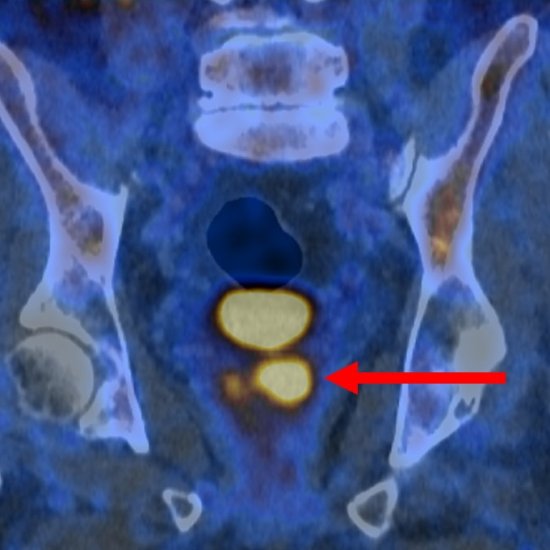

News • Nuclear imaging in urology

A PSMA PET/CT imaging test could safely halve the number of people who need a biopsy for suspected prostate cancer following inconclusive or reassuring results from an MRI scan, new research finds. |